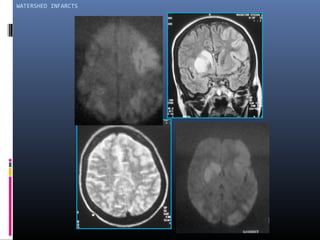

Watershed infarcts

 Junction of large arterial territories

 Chronic large vessel stenosis precipitated by

hypotension

 DWI , PW helpful in etiology

MORE COMMONLY HEMORRHAGIC